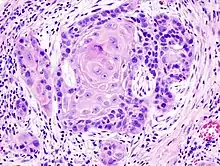

Squamous cell carcinoma of the mouth

Squamous cell cancers are common in areas of the mouth, including the inner lip, tongue, floor of the mouth, gums, and hard palate. Cancers of the mouth are strongly associated with tobacco use, especially the use of chewing tobacco or dipping tobacco, as well as heavy alcohol use. Cancers of this region, particularly the tongue, are more frequently treated with surgery than other head and neck cancers. Lip and oral cavity cancers are the most commonly encountered types of head and neck cancer.[5]